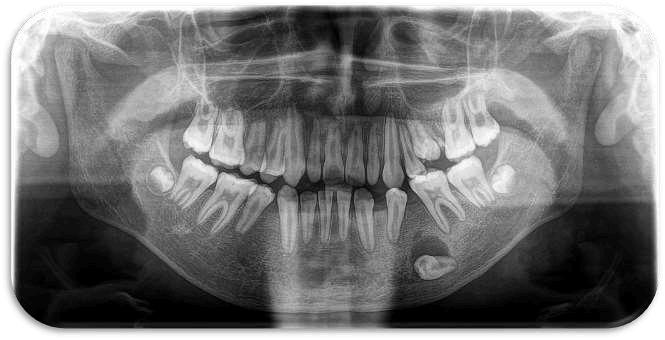

El quiste de retención mucoso del seno maxilar es una lesión benigna, generalmente asintomática, que se detecta de manera incidental en estudios radiográficos. Se presenta el caso de un paciente en el que, durante una radiografía panorámica de rutina, se identificó una imagen radiopaca bien delimitada en seno maxilar izquierdo compatible con quiste de retención mucoso Se discuten las características radiográficas, el diagnóstico diferencial y las consideraciones clínicas en el manejo de este hallazgo

Reporte de caso

Paciente masculino, de 35 años, acude para valoración odontológica general Se realizó radiografía panorámica como parte del examen inicial En el seno maxilar izquierdo se observó una imagen radiopaca de límites definidos, redondeada, localizada en la pared inferior del seno No se observaron signos de destrucción ósea ni desplazamiento de estructuras adyacentes

El paciente no refirió síntomas respiratorios ni dolor en la región. Con base en las características radiográficas, el hallazgo fue diagnosticado como quiste de retención mucoso en seno maxilar izquierdo. Se indicó control clínico y tomografía, al no requerir tratamiento quirúrgico inmediato.

Introducción

El QRM es una entidad benigna, autolimitada y habitualmente asintomática. Radiográficamente se presenta como una opacidad homogénea, redondeada, en el interior del seno maxilar, sin comprometer la arquitectura ósea.

El diagnóstico diferencial incluye sinusitis crónica, pólipos antrales y lesiones quísticas odontogénicas que invaden el seno Sin embargo, la ausencia de sintomatología y la apariencia radiográfica típica orientan hacia un QRM

La mayoría de los casos no requiere tratamiento, siendo suficiente el seguimiento clínico-radiográfico

El quiste de retención mucoso del seno maxilar es un hallazgo frecuente en radiografías panorámicas de rutina Su reconocimiento es importante para evitar diagnósticos erróneos y procedimientos innecesarios El seguimiento radiográfico constituye la conducta adecuada en pacientes asintomáticos